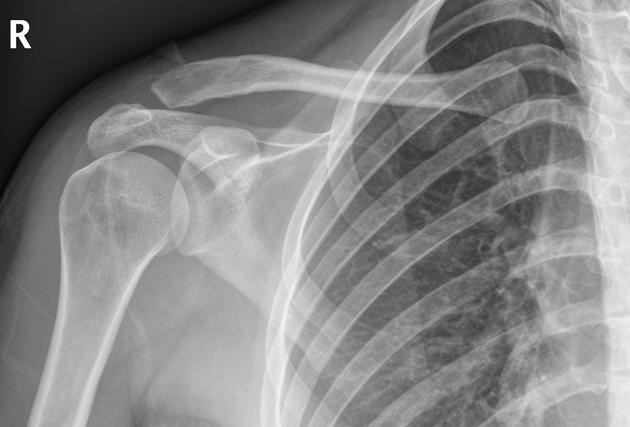

Based off Rockwood classification of acromioclavicular joint injury, what grade would this be?

3